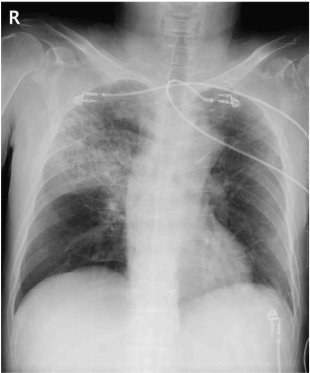

58세 남자가 4일 전부터 고열과 누런 가래가 있다며 병원에 왔다. 30갑•년의 흡연력이 있으며, 8년 전부터 금연하고 있다. 혈압 110/80 mmHg, 맥박 100회/분, 호흡 22회/분, 체온 38.6℃이다. 오른쪽 가슴에서 거품소리가 들린다. 가슴 X선 사진이다. 혈액검사 결과는 다음과 같다. 치료는?

CXR: RUL lobar consolidation

• 오른쪽 가슴에서 거품소리 들리므로 폐렴을 의심할 수 있으며, 혈액검사에서도 염증성 질환을 시사하는 leukocytosis가 관찰된다. 나아가 CXR상 RUL lobar consolidation이 저명하게 관찰되므로 폐렴으로 진단할 수 있다.

• 해당 증례의 경우 증상이 급성 병색으로 발생하였고 발열과 함께 호흡기 증상이 두드러지며, 영상 소견상 lobar consolidation이 저명하게 관찰되는 점, 혈액검사에서 백혈구 증가가 관찰된다는 점은 정형 폐렴의 임상 양상과 부합한다. 따라서 비정형 폐렴의 증거를 확인할 수 없는 바 respiratory fluoroquinolone, beta-lactam 단독투여 beta-lactam인 아목시실린-클라불라네이트를 사용한다.